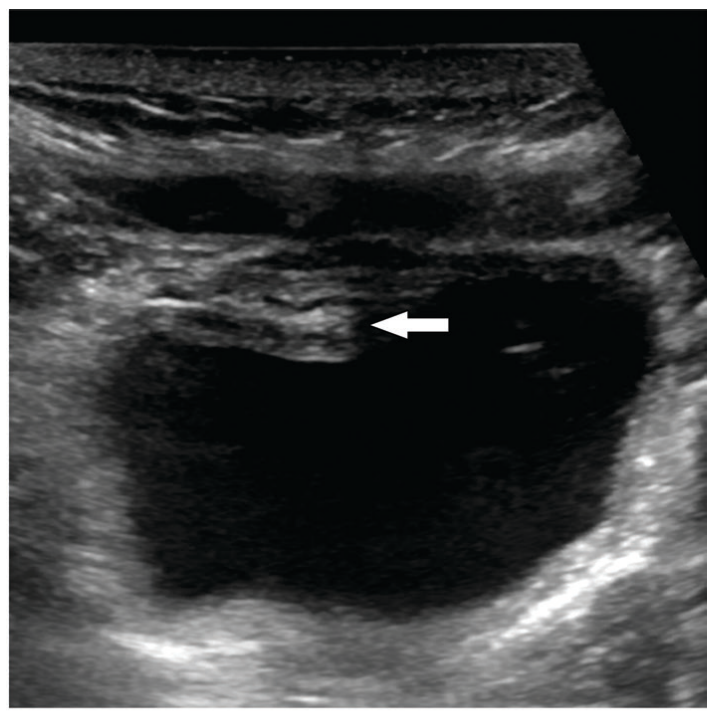

Name this artifact.

What is the cause of the artifact?

Slice thickness/Volume Averaging Artifact – if two structures of differing attenuation are present in the same slice width, their intensities are averaged

Example: pseudosludge